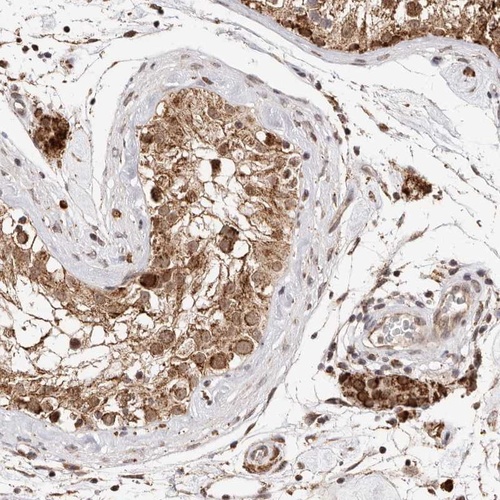

Immunohistochemical staining of human testis shows strong cytoplasmic positivity in Leydig cells.